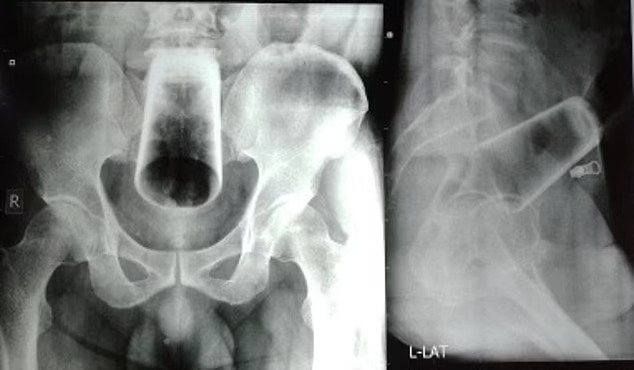

Sau khi thăm khám, các bác sĩ cho biết, tâm trạng và hành vi của người đàn ông 47 tuổi đã ổn định, người này cũng được xác định không có tiểu sử bệnh tâm thần trước đây. Ảnh chụp X-quang vùng hậu môn nạn nhân cho thấy một chiếc cốc thủy tinh úp ngược được nhét sâu vào trong trực tràng và đại tràng của nạn nhân.

Các bác sĩ sau đó đã phải tiến hành ca phẫu thuật mở ruột sigma với một vết rạch ở đại tràng để lấy chiếc cốc ra do không thể lấy dị vật bằng tay, đồng thời cũng có những lo ngại việc này có thể khiến chiếc cốc sẽ bị vỡ.